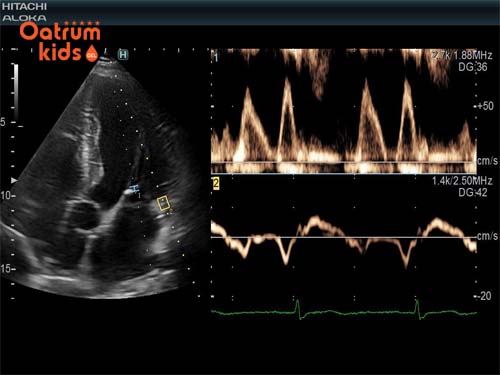

Với sự phát triển như vũ bão của khoa học công nghệ, các thiết bị tân tiến này cũng được áp dụng trong ngành y. Điển hình là thiết bị cầm tay Doppler cho phép có thể nghe được nhịp tim của thai nhi và xác định rõ được nhịp tim là bao nhiêu. Doppler là thiết bị nghe sử dụng công nghệ siêu âm và sóng âm thanh giúp xác định âm thanh nhịp tim của bé.

Thiết bị Doppler có khả năng nghe được tim của em bé khi thai nhi được 10 -12 tuần tuổi và được sử dụng để nghe nhịp tim cho đến tận ngày mẹ chuyển dạ, giúp xác định kiểm tra tình hình sức khỏe của thai nhi. Còn với những thai nhi mà vào tuần thứ 5-6 thai kỳ thì chỉ có thể nghe nhịp tim của bé qua siêu âm như siêu âm thai qua ngả âm đạo hoặc là siêu âm transabdominal, tùy vào tuổi thai và lượng mỡ dưới da mà chọn cách phù hợp.

Những nhịp tim đầu tiên của thai nhi thường khó chẩn đoán hơn nhưng ngày nay công nghệ siêu âm trong tam cá nguyệt đầu tiên được cải thiện thì chỉ cần thai được 6-7 tuần tuổi là có thể thấy được một vài điểm nhấp nháy trên màn hình siêu âm.

Nhịp tim của thai nhi sẽ có sự dao động theo từng thời gian. Cụ thể khoảng từ 8-10 tuần thì trái tim của bé sẽ đập tầm khoảng 170-200 nhịp mỗi phút (bpm). Nhưng đến giữa hoặc cuối thai kỳ thì nhịp tim chậm hơn, chỉ tầm từ 120-160 bpm/phút.